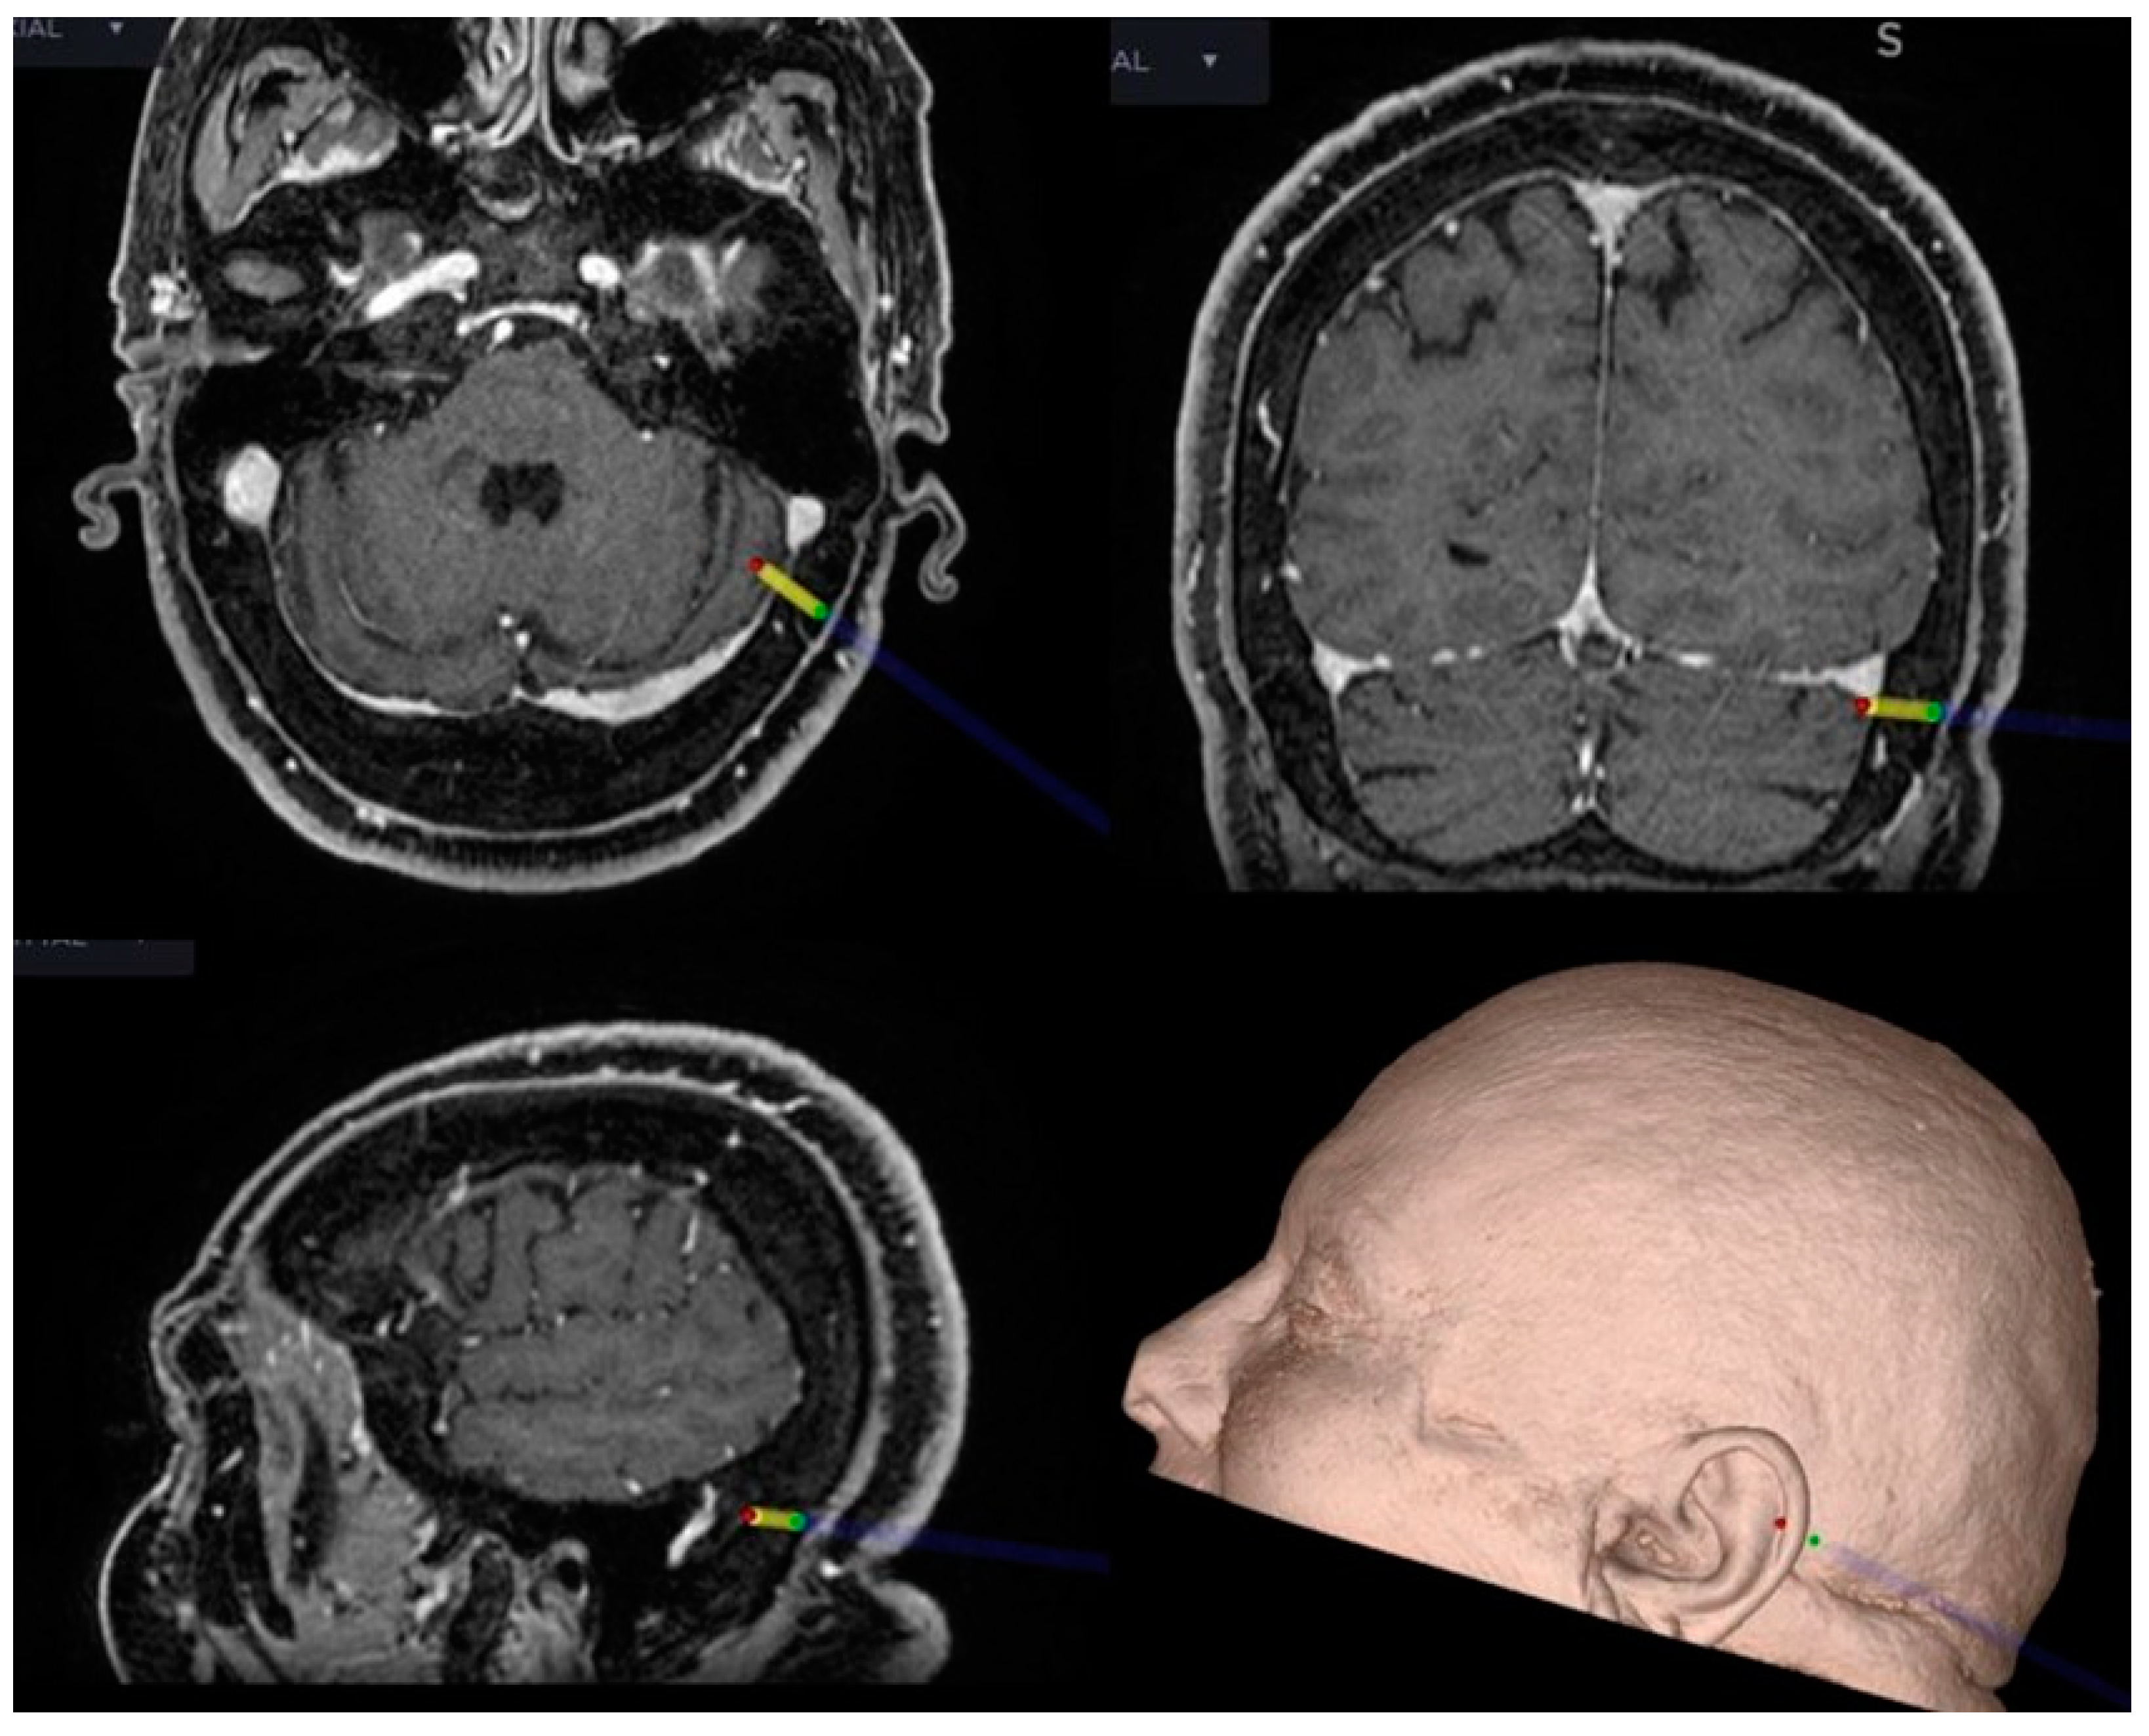

2.1. Neuronavigation